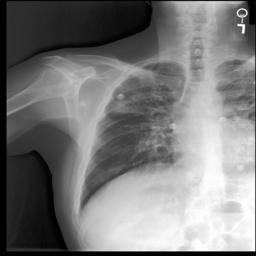

5.2 Visualization of attention weights

Fig. 5 presents a qualitative visualization of the learned word-to-region correspondences facilitated by our AGA framework. The top row shows the original medical images, including both chest X-rays (CXR) and endoscopic ultrasound (EUS) images. The bottom row displays the corresponding heatmaps generated by our model, where warmer colors denote higher activation weights, indicating stronger associations between specific image regions and the given medical concepts. For Atelectasis and Pneumonia, the model focuses on appropriate pulmonary regions, demonstrating strong localization aligned with radiological pathology. For the SMTs domain, terms like low-echoic mass and protruded into the cavity activate precisely the relevant interior structures of the lesion in EUS images. The distinct and interpretable activation patterns validate the effectiveness of our AGA mechanism in achieving fine-grained multimodal alignment.

Atelectasis

Pneumonia